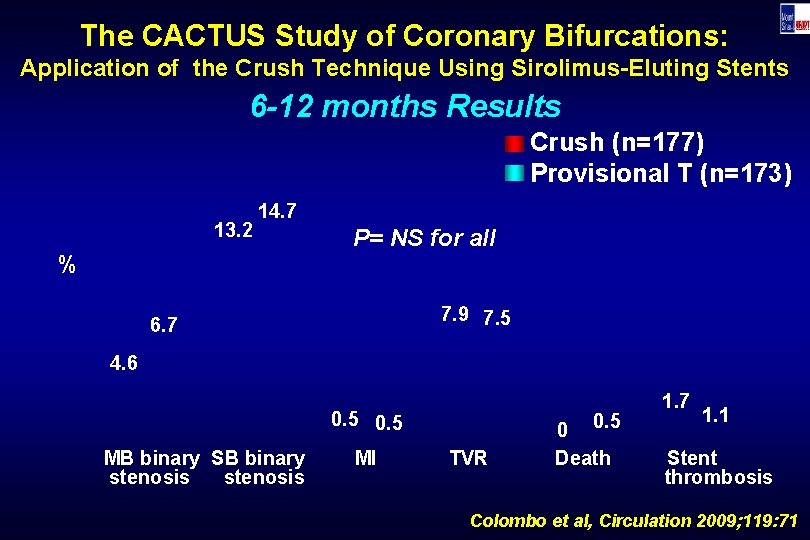

The CACTUS Study of Coronary Bifurcations: Application of the Crush Technique Using Sirolimus-Eluting Stents 6 -12 months Results Crush (n=177) Provisional T (n=173) 13. 2 14. 7 % P= NS for all 7. 9 7. 5 6. 7 4. 6 0. 5 MB binary SB binary stenosis MI 0. 5 TVR 0 Death 1. 7 1. 1 Stent thrombosis Colombo et al, Circulation 2009; 119: 71